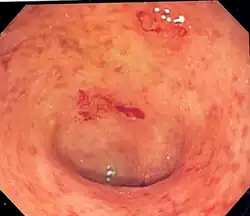

| Endoscopic image of a colon affected by ulcerative colitis. The internal surface of the colon is blotchy and broken in places. Mild-moderate disease. | |

The best test for the diagnosis of ulcerative colitis remains endoscopy, which is the examination of the internal surface of the bowel using a flexible camera. Initially, a flexible sigmoidoscopy may be completed to establish the diagnosis.[73] The physician may elect to limit the extent of the initial exam if severe colitis is encountered to minimize the risk of perforation of the colon. However, a complete colonoscopy with entry into the terminal ileum should be performed to rule out Crohn's disease and assess the extent and severity of the disease.[73] Endoscopic findings in ulcerative colitis include: erythema (redness of the mucosa), friability of the mucosa, superficial ulceration, and loss of the vascular appearance of the colon. When present, ulcerations may be confluent. Pseudopolyps may be observed.[74]